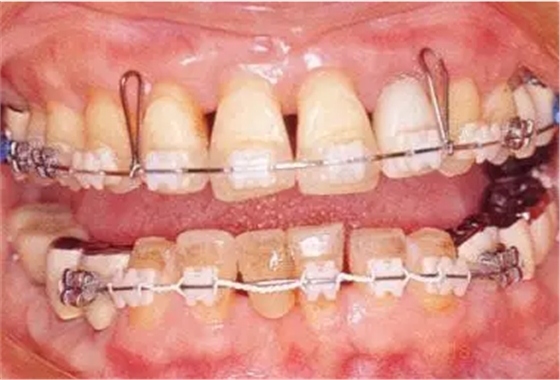

▲圖19-7

正畸治療完成時。

▲圖19-8,9

▲圖19-8 佩戴臨時修復體。即使在這個狀態(tài)下,依然有牙周袋殘留。

▲圖19-9 完成牙周外科治療后的狀態(tài)。